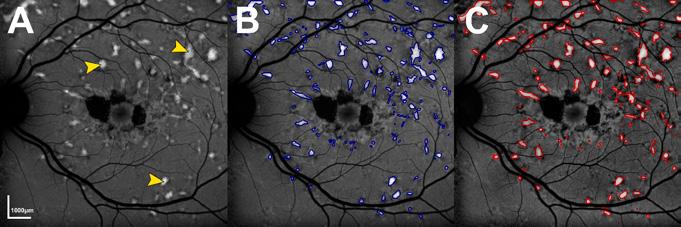

The retina, a light-sensitive layer at the back of the eye, is responsible for processing light signals crucial for vision. With multiple sublayers and cell types, it is one of the most intricate structures in the human body. Eye care health professionals use a variety of imaging techniques in order to assess its structure and function. Central (Figure 1A)

and wide-field (Figure 1C) photographs capture en face views of the retina, while cross-sectional scans, such as optical coherence tomography (OCT), reveal retinal sublayers (Figure 1B). Different wavelengths of light can also be used to infer retinal health and metabolism (Figures 1D and 1E).

Figure 1: A healthy retina imaged by different modalities. (A) Photograph of the central retina. (B) Optical coherence tomography, demonstrating various retinal sublayers. (C) Widefield pseudocolour photograph. (D) Fundus autofluorescence image of the central retina using short-wavelength light. (E) Fundus autofluorescence image of the central retina using near-infrared light.

An overview of this workflow is illustrated in Figure 3, where multimodal retinal images and patient data are processed through XAI models to generate predictions of a patient’s future visual function, while also highlighting the retinal regions driving these predictions.

researchers’ explainable artificial intelligence (AI) workflow for inherited retinal disease. This research sits at the intersection of technological innovation and medical advancement. The rapid evolution of AI, imaging technologies, and genomic analysis is transforming how we understand and treat complex diseases. By harnessing these tools, we are not only improving diagnostic accuracy but also enabling earlier interventions and more tailored treatment strategies.

Figure 2: Example of artificial intelligence (AI)-facilitated segmentation of hyperautofluorescent flecks in Stargardt disease. (A) Short-wave autofluorescence image of an eye with Stargardt disease. Pointers indicate examples of hyperautofluorescent flecks. (B) Flecks segmented by an AI algorithm. (C) Manually segmented flecks.

Figure 3: Example of the